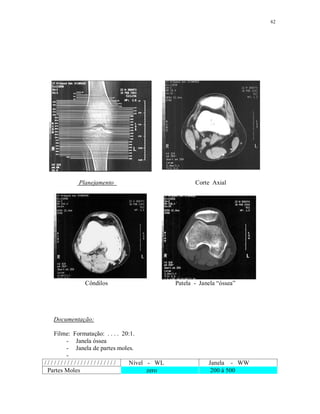

Planejamento:

Níveis L3-L4 / L4-L5 / L5-S1 Pedículos / Saco dural.

Forames intervertebrais “Janela Óssea “

Documentação:

Filme formatado 20:1 - Com referências dos níveis de corte.

Janela de partes moles.

Janela óssea.

/ / / / / / / / / / / / / / / / / / / / / / Nível - WL Janela - WW

Partes Moles 30 200 à 400

Janela óssea 200 2000